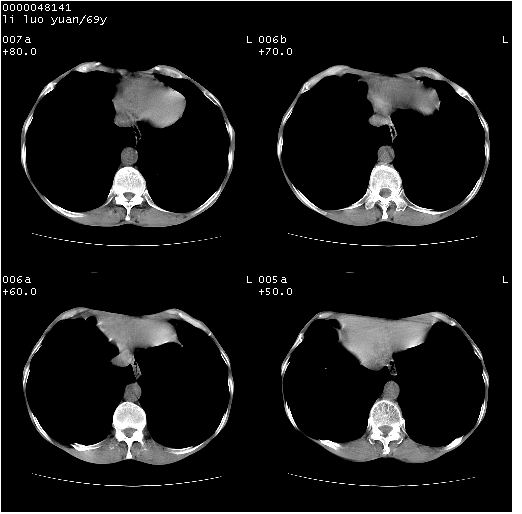

临床资料:老年患者,咯血、消瘦

影像表现:桶状胸,双肺纹理纤细、紊乱,透过度增高,肺野内可见多发、散在、大小不等的无壁高透过影,右肺中叶外侧段分叶样软组织占位,左上肺纤维索条样密度影,相应层面左侧胸腔轻度萎陷,纵隔左移。

影像诊断:1、慢支、肺气肿、双下肺野肺大泡形成

2、左上肺陈旧性肺结核

3、右肺中叶外侧段占位 考虑肺ca可能性较大、建议增强及痰检脱落细胞